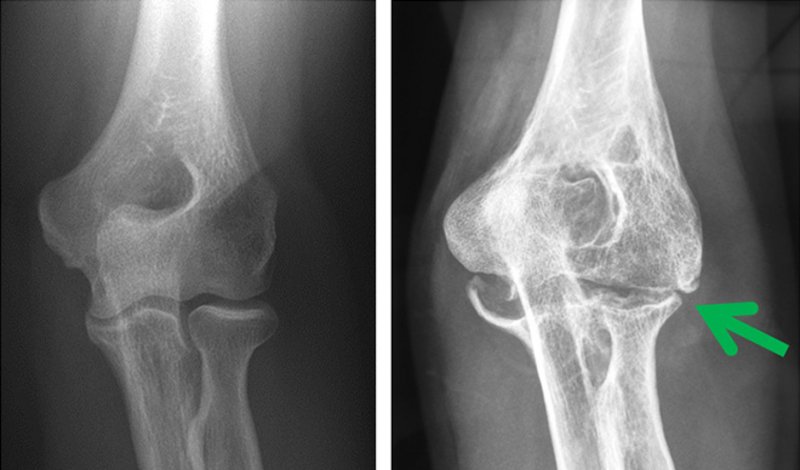

Falls der Bruch mehr als 1/3 der Gelenkfläche umfasst und die Verschiebung größer ist als 2 mm, wird eine Reposition und Stabilisierung empfohlen.

Die beiden Röntgenbilder rechts zeigen das angehobene Fragment und die Minischrauben-Osteosynthese (#).